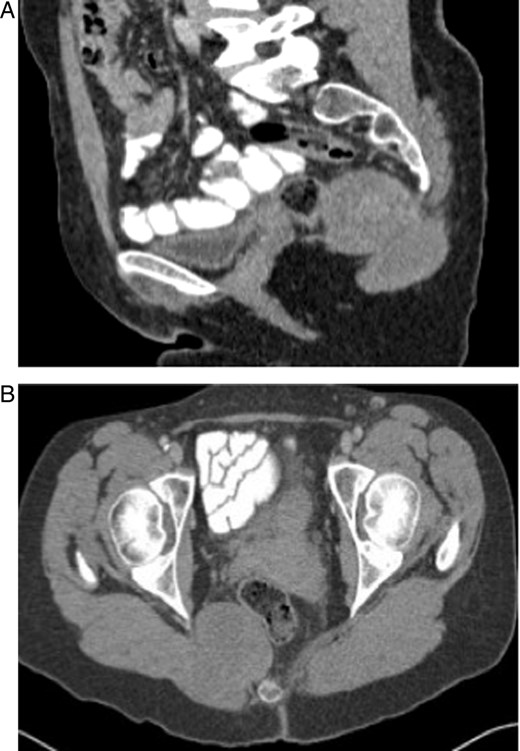

A 59-year-old lady presented with a 6-month history of a large, painless swelling in her right buttock with an associated change in bowel habit towards looser stools. On physical examination, there was a palpable, firm, fixed swelling of 4 × 3 cm in the right peri-anal region about 3 cm from the natal cleft. On digital rectal examination, the mass was palpable low down on the borders of the sacrum and coccyx. CT colonography showed a 9 cm × 5.6 cm × 4.5 cm lesion arising from the right medial aspect of her gluteus maximus, which displaced the mesorectal fascia and externally compressed the rectum. CT Pelvis showing a bilobed mass on the right side lying in the ischiorectal fossa extending out through the greater sciatic notch into the buttock measuring 9 cm × 6 cm × 4.5 cm (Fig. 1A and B).

(A and B) CT scans of the tumour showing a bilobed mass within the ischiorectal fossa extending through the greater sciatic notch.